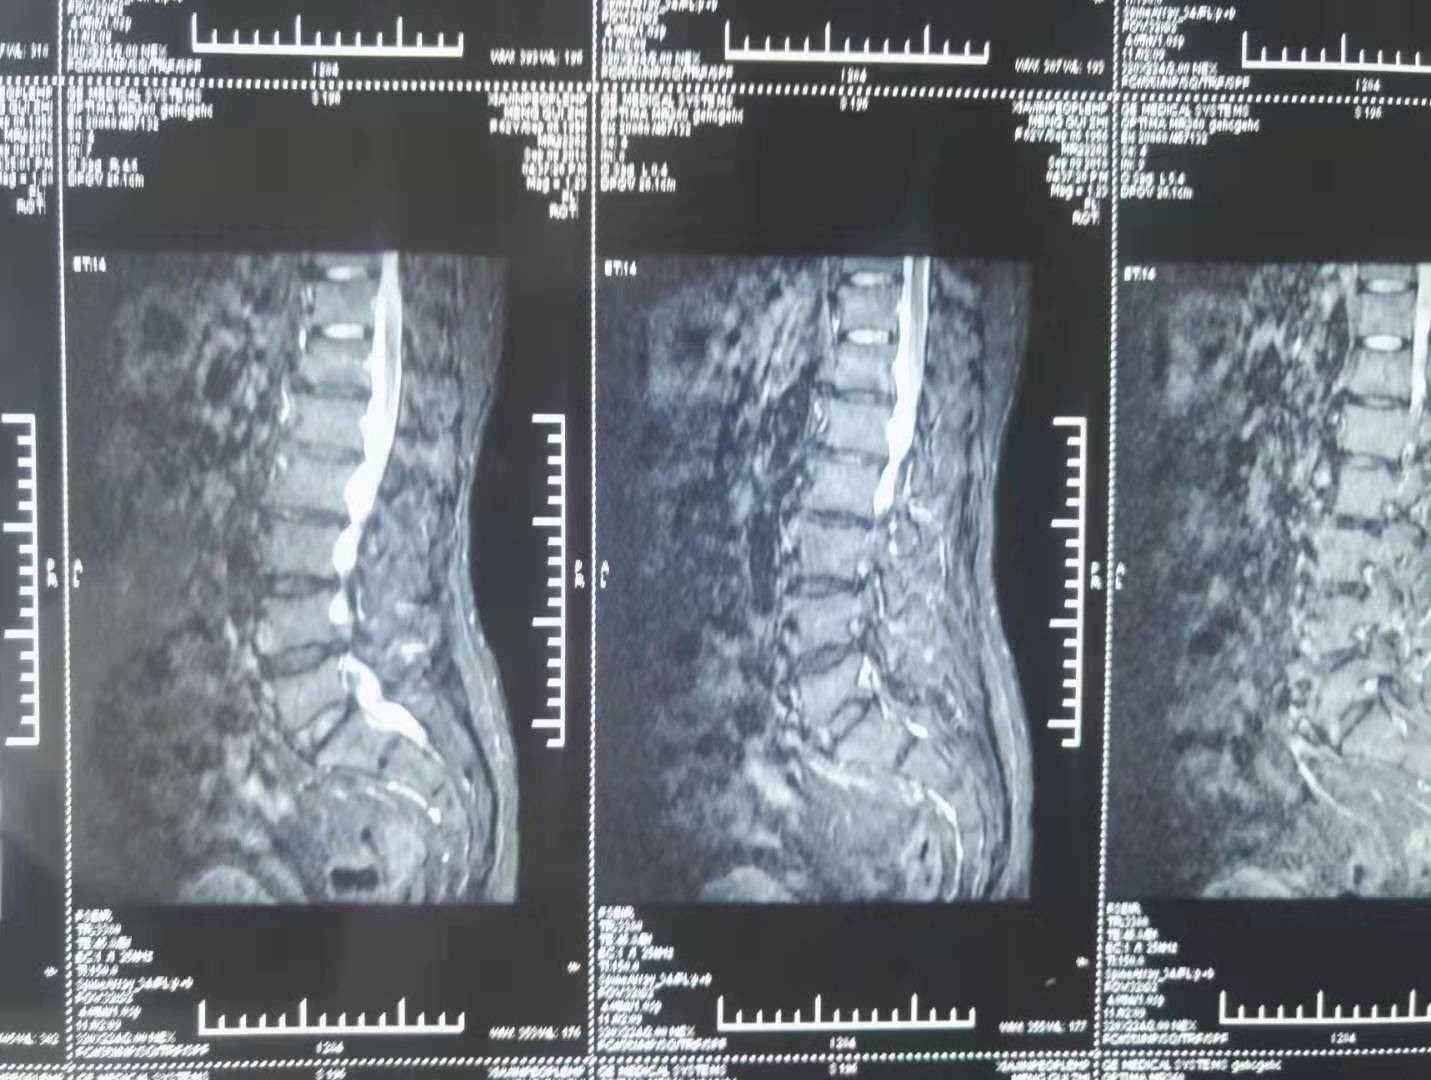

经典医案13

2022.08.03